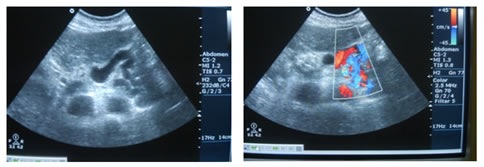

Figure 1: USG Axial image showing Dilated Portal Vein; Figure 2: USG Axial image showing Loss of Respiratory variations in Portal Vein diameter; Figure 3: Colour Doppler showing Flow reversal in Splenic vein; Figure 4: Colour Doppler Axial image: Flow reversal in SMV shown by arrow; Figure 5: USG Axial image showing dampened flow in Portal vein; Figure 6: HRUS image showing Nodular liver surface in cirrhosis